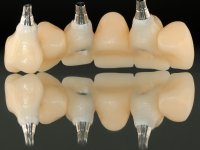

O paciente foi observado conjuntamente e a dúvida que surgiu de imediato foi se seria possível com a regeneração óssea a efectuar poder ser reabilitada naturalmente a zona das papilas interdentárias. Nesse sentido foi feito um enceramento de diagnóstico que contemplaria as duas hipóteses, utilizando ou não a cerâmica gengival. A confecção desse enceramento foi fundamental para expor ao paciente a dificuldade da reabilitação. O wax-up deu origem a um mock-up que foi aprovado pelo paciente e que simultaneamente serviu de guia imagiológica. O caso foi planificado cirurgicamente e realizada uma guia cirúrgica com que foram colocados os implantes. Após 10 semanas foi feita a 1ª impressão para confecção da ponte provisória. Foram criados os primeiros perfis de emergência na gengiva artificial e foi digitalizado o modelo. Por processo de CAD-CAM foi confeccionada uma ponte provisória aparafusada baseada no enceramento de diagnóstico. A ponte trabalhou durante 8 semanas os tecidos moles que foram fielmente copiados numa impressão com técnica de moldeira aberta. Os transferes foram individualizados com resina composta para copiarem fielmente os perfis de emergência criados pela ponte provisória. Confeccionado o modelo de trabalho definitivo, foi realizada uma infra-estrutura em zircónio seguindo a orientação do enceramento de diagnóstico. O assentamento da infra-estrutura foi testado em boca e simultaneamente foi novamente impressionados os tecidos moles com um silicone fluido. Nessa consulta foi feito o levantamento da cor. Os dentes 13 e 23 apresentavam uma saturação anormalmente forte que resolvemos não valorizar, optando por privilegiar a relação com o sector antero-inferior. Foi realizada uma nova gengiva artificial com a impressão que acompanhou a impressão de arrasto com a infra-estrutura. Após a colocação da cerâmica na infra-estrutura foram coladas as meso-estruturas. O trabalho final foi aparafusado lentamente permitindo a adaptação dos tecidos moles.